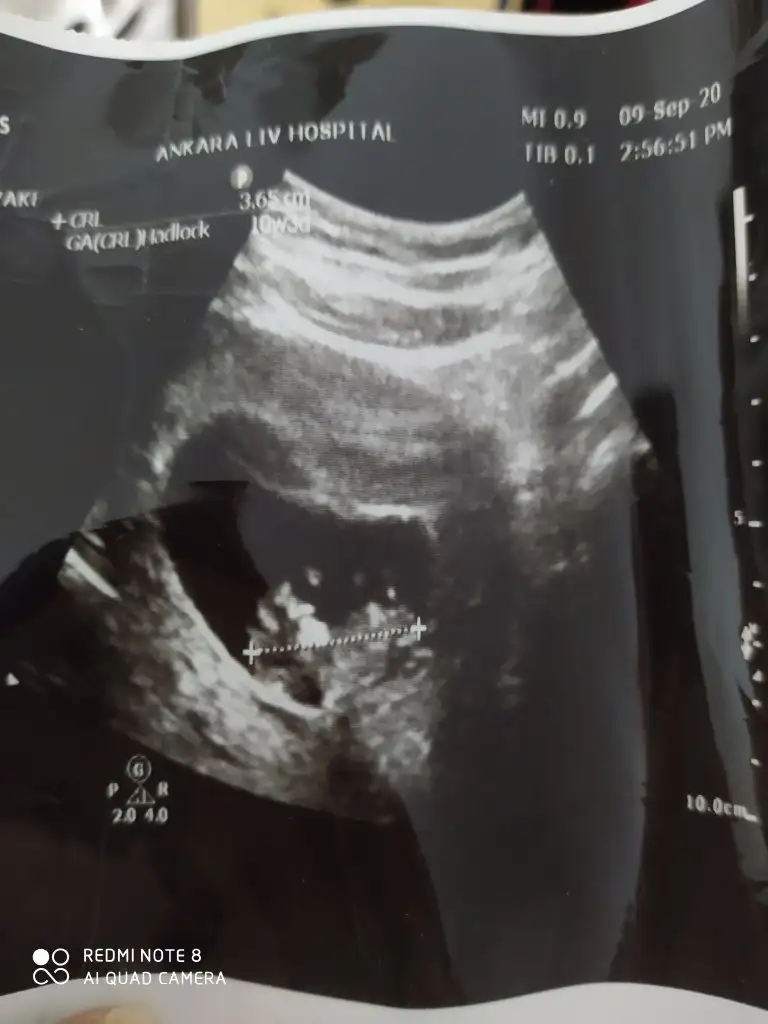

E bu benimkiyle aynıIkra meyra cığım benim diğer görüntüme kız dedin. Bi de bu açıyı göndereyim bu ne olabilir

Ya bana da kız gibi geliyor bizimki. Sizin doktor tahminde bulundu mu?Ay dünden beri bakıyorum bakıyorum anlayamadım,açıkça anlayamıyorsak zaten kızdır kesin30 ekimde net öğrenicez o zaman anketini de oylayacağım büyük ihtimalle kız evet, benim canım kızım